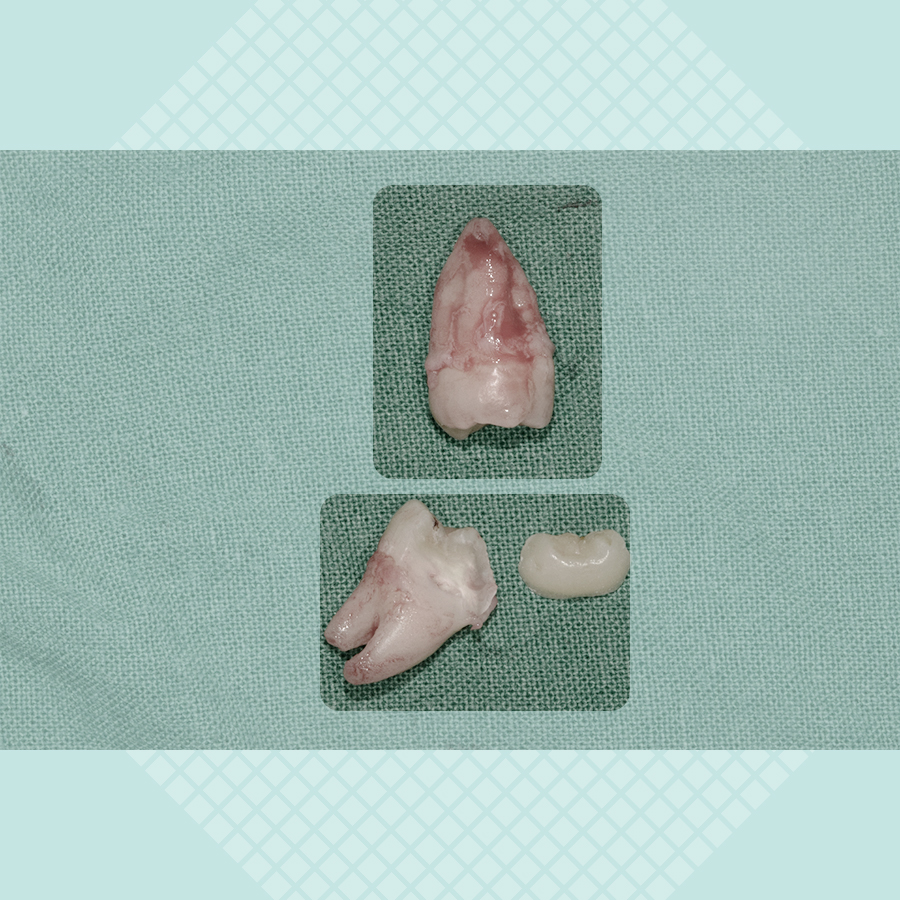

마취를 한 뒤 뼈는 건드리지 않고 사랑니 일부분만 쪼갠 후 엘리베이터라는 얇고 길쭉한 도구로 살짝 돌리니 툭 하고 아래 사랑니발치가 쉽게 끝이 났어요, 위 쪽은 포셉으로 잡으니까 슥 뽑혔구요. 이 모든 과정이 10분 남짓! 조금 놀라셨는데 역시 강남레옹치과는 다르다는 생각을 하셨대요^^

빠르게 잘 나온 두 치아. 본인 사례가 복잡하고 어려워 걱정했던 것이 무색할 정도로 간단하게 발거가 되었네요. 이 경우는 치관의 1/3이 잇몸 아래로 묻혀 있어 단순매복으로 인정, 뿌리 끝이 신경관가 닿아서 찍은 CT를 합쳐서 토탈 4~5만원 정도로 비용이 나왔죠.